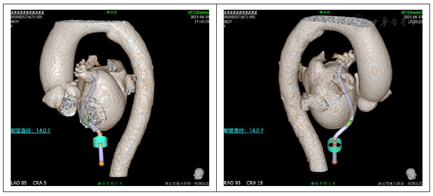

术后患者一般情况可,术后2月余复查CT(图10)提示左心耳封堵完全,未见残余分流,封堵器位置良好,上缘轻度露肩,未见器械相关血栓发生,遂停用达比加群,予以双联抗血小板药物进行治疗。

PREVAIL研究已证实即便在无植入经验的医生及中心,LAAC手术的置入成功率及围术期安全性均较高[2]。但由于左心耳形态多变,术前仍需要进行充分影像学评估左心耳的结构特点,以制定合适的手术策略。目前常用的影像学评估手段主要为经食道超声心动图、多排螺旋CT、心腔内超声及数字检影血管造影。多排螺旋CT基于非侵入性、高分辨率的特点和重建心房及其周边解剖结构三维模型的强大能力,为术者提供了LAA的详细特征,成为术前决策、术中指导和术后随访的得力工具[3]。在本例患者的治疗过程中,我们通过术前CT检查明确了左心耳的结构为低位反鸡翅型,同时心耳开口偏小,深度较浅,此类心耳在进行封堵时难度较大,而通过术前CT结果模拟明确了左心耳不同分叶的大小、封堵器大小、封堵轴向及穿刺部位的选择,针对此患者在术前设计好封堵策略,通过术中精细操作,最终完成了该例高难度左心耳的封堵手术。同时术后CT进行封堵效果随访,使得术者可以直观了解封堵器植入后的形态,并明确是否存在残余分流,测量露肩高度,判断封堵器上是否内皮化有无残余血栓,同时也减少了随访时TEE的使用,提高了患者的舒适性。